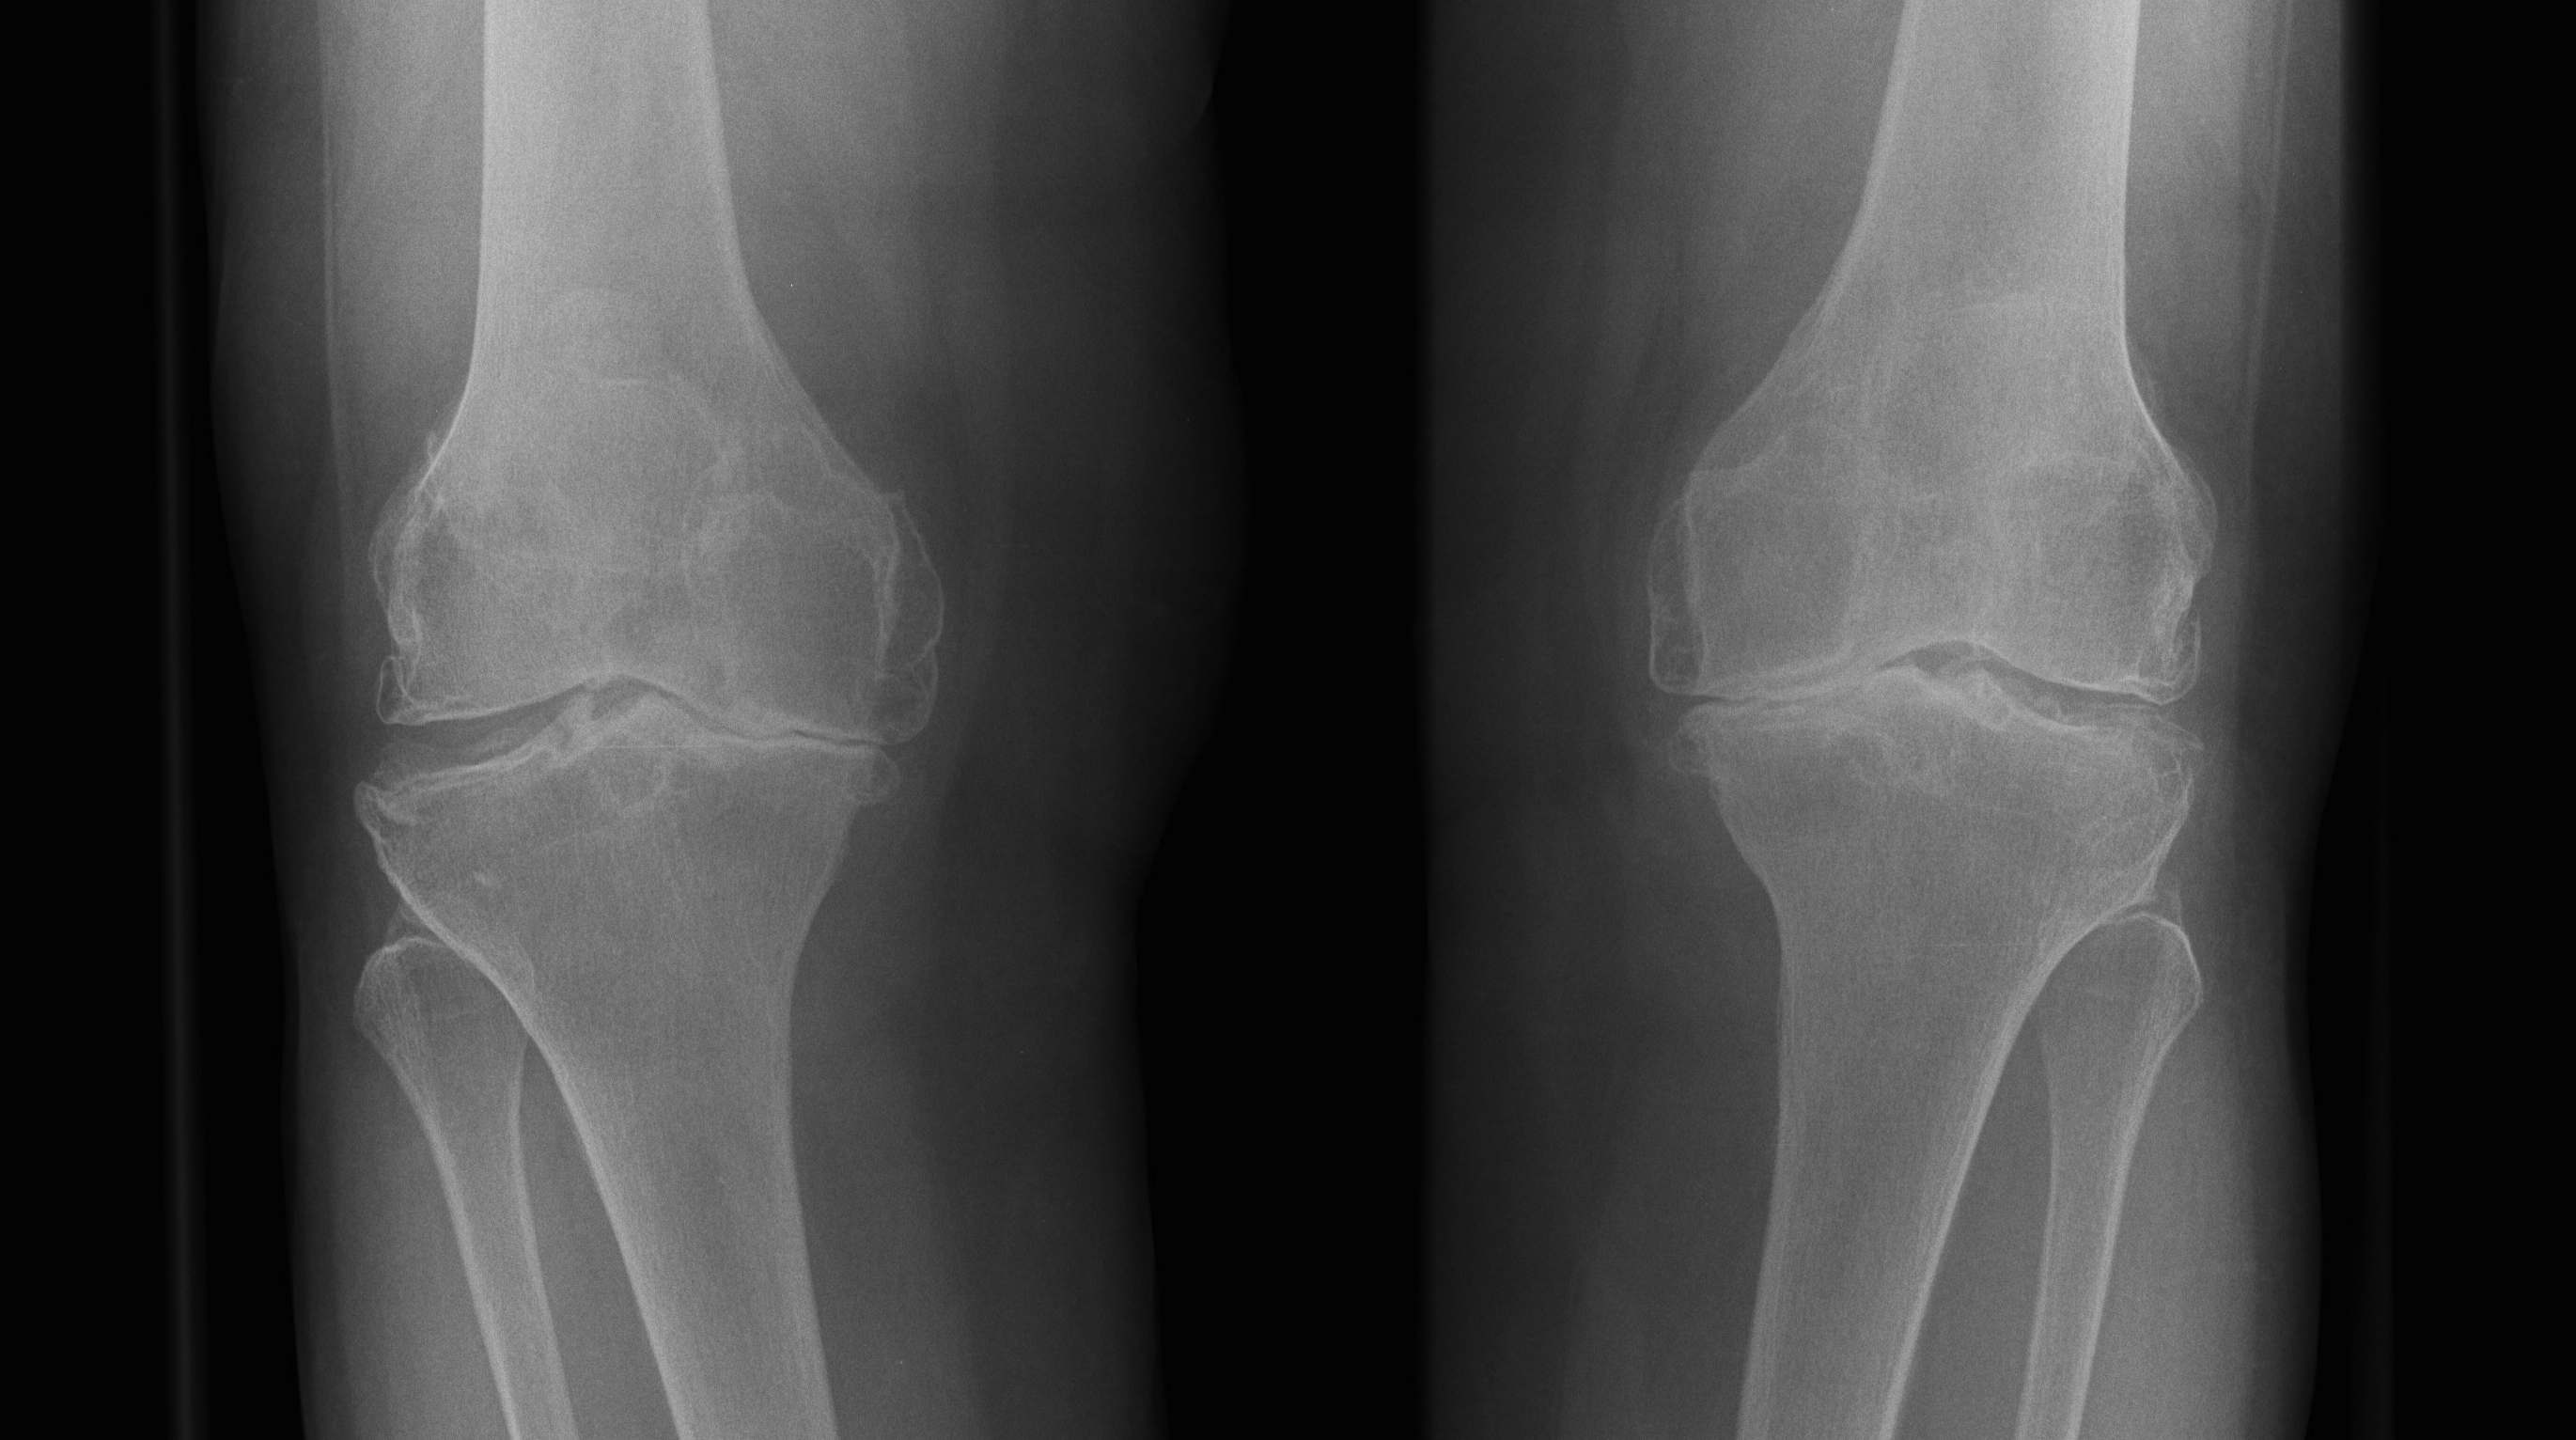

Indications

Unable to use femoral / tibial IM or EM Jigs

- fracture / metal work / deformity

Bilateral TKR

- reduce post op confusion in patient

- from bilateraly IM rod

Young patient < 65

- attempt to achieve perfect alignment / balancing

- want TKR to survive long term